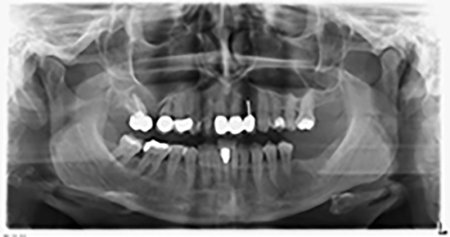

Al fine di pianificare e minimizzare i rischi, circa sei mesi dopo l'estrazione dei denti 16 e 14 viene effettuata una tomografia digitale volumetrica (DVT, Planmeca), la quale conferma chiaramente la mancata rigenerazione ossea nel volume desiderato (da fig. 2 a 7).

Da immagine 2 a 7: DVT con volume osseo orizzontale notevolmente ridotto.

È necessario un rialzo del pavimento sinusale nelle regioni 16 e 14 per garantire una solida ricostruzione basata su almeno due impianti. Si auspica un accrescimento osseo su scala relativamente ampia a causa del volume osseo residuo estremamente ridotto in questo caso. Le principali procedure di accrescimento osseo sono invasive e incrementano il tasso di morbilità dei pazienti, oltre a essere costose in termini di tempo e denaro. Prevedere l'esito del trattamento diventa più difficile e il rischio di insuccesso aumenta. Il dentista informa la paziente e le propone una soluzione asportabile, fermamente rifiutata.

Per ridurre l'accrescimento nella regione 14, con il consenso della paziente si opta per il posizionamento e l'inclinazione dell'impianto 16 in direzione dorso-craniale (fig. 8).